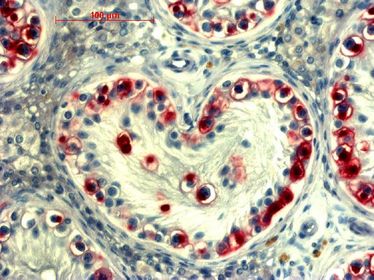

CeRA Seminar: Testis Cancer

CeRA Seminar: Testis Cancer